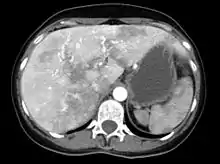

The symptoms produced by AVMs in the liver depend on the type of abnormal connection that they form between blood vessels. If the connection is between arteries and veins, a large amount of blood bypasses the body's organs, for which the heart compensates by increasing the cardiac output. Eventually congestive cardiac failure develops ("high-output cardiac failure"), with breathlessness and leg swelling among other problems.[1][6] If the AVM creates a connection between the portal vein and the blood vessels of the liver, the result may be portal hypertension (increased portal vein pressure), in which collateral blood vessels form in the esophagus (esophageal varices), which may bleed violently; furthermore, the increased pressure may give rise to fluid accumulation in the abdominal cavity (ascites). If the flow in the AVM is in the other direction, portal venous blood flows directly into the veins rather than running through the liver; this may lead to hepatic encephalopathy (confusion due to portal waste products irritating the brain). Rarely, the bile ducts are deprived of blood, leading to severe cholangitis (inflammation of the bile ducts).[1][6] Liver AVMs are detectable in over 70% of people with HHT, but only 10% experience problems as a result.[2]

Liver AVMs may be suspected because of abnormal liver function tests in the blood, because the symptoms of heart failure develop, or because of jaundice or other symptoms of liver dysfunction. The most reliable initial screening test is Doppler ultrasonography of the liver; this has a very high sensitivity for identifying vascular lesions in the liver. If necessary, contrast-enhanced CT may be used to further characterize AVMs.[1][2][6] It is extremely common to find incidental nodules on liver scans, most commonly due to focal nodular hyperplasia (FNH), as these are a hundredfold times more common in HHT compared to the general population. FNH is regarded as harmless. Generally, tumor markers and additional imaging modalities are used to differentiate between FNH and malignant tumors of the liver. Liver biopsy is discouraged in people with HHT as the risk of hemorrhage from liver AVMs may be significant.[6][7] Liver scans may be useful if someone is suspected of HHT, but does not meet the criteria (see below) unless liver lesions can be demonstrated.[7]

Given that liver AVMs generally cause high-output cardiac failure, the emphasis is on treating this with diuretics to reduce the circulating blood volume, restriction of salt and fluid intake, and antiarrhythmic agents in case of irregular heart beat. This may be sufficient in treating the symptoms of swelling and breathlessness. If this treatment is not effective or leads to side effects or complications, the only remaining option is liver transplantation. This is reserved for those with severe symptoms, as it carries a mortality of about 10%, but leads to good results if successful.[6][7] The exact point at which liver transplantion is to be offered is not yet completely established.[6] Embolization treatment has been attempted, but leads to severe complications in a proportion of patients and is discouraged.[5][6][7]

Other liver-related complications (portal hypertension, esophageal varices, ascites, hepatic encephalopathy) are treated with the same modalities as used in cirrhosis, although the use of transjugular intrahepatic portosystemic shunt treatment is discouraged due to the lack of documented benefit.[6]